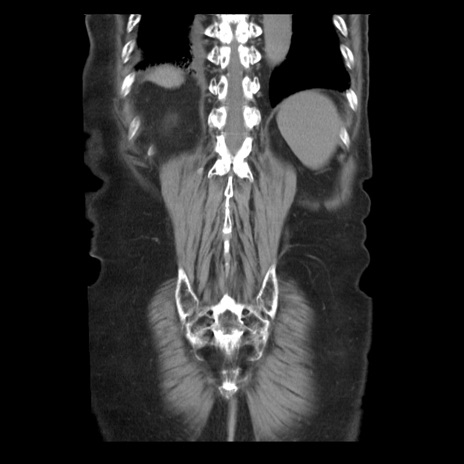

症例21(冠状断像)

【症例】70歳代男性

【主訴】腹痛

【現病歴】肝硬変・肝細胞癌にてかかりつけの方。約9時間前に食後より腹痛出現。症状が徐々に増悪し、嘔吐出現したため来院。

【既往歴】肝硬変、肝細胞癌(RFA、TACE後)

【身体所見】意識清明、表情苦悶様、BT 36℃、BP 129/78mmHg、P 88bpm、SpO2 97%(RA)、右上腹部から心窩部にかけて圧痛あり、反跳痛なし、筋性防御あり。

【データ】WBC 5800、CRP 0.16